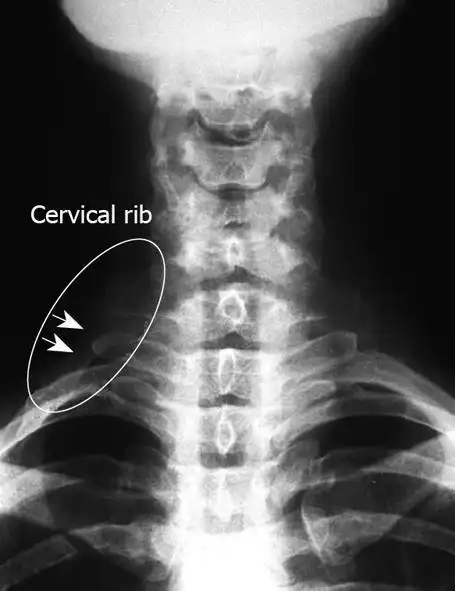

70岁.很典型的颈肋.

双侧颈肋并肋骨间骨性联合